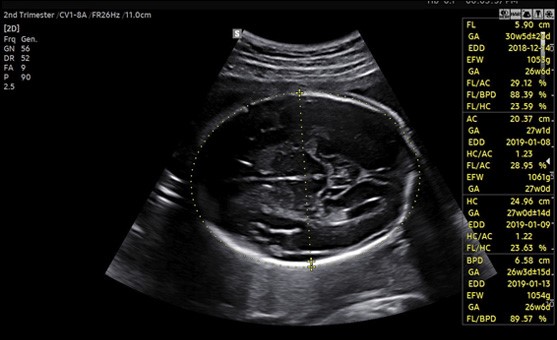

Samsung Medison BiometryAssist™ выполняет автоматическое измерение и оценку размеров плода с точностью 97% в один клик мыши, затрачивая на это примерно 85 миллисекунд. Такая скорость работы позволяет врачу принимать большее количество пациентов и уделять больше времени для общения с ними.

Технология BiometryAssist™, созданная Samsung Medison – это полуавтоматическая система измерения и оценки размеров плода с точность 97-99%. Такая высокая эффективность позволяет использовать решение в современной клинической практике

- прокомментировал доктор медицинских наук, профессор Джа-Ён Квон (Ja-Young Kwon) департамента акушерства и гинекологии Медицинского колледжа Университета Йонсей в Сеуле, Корея.